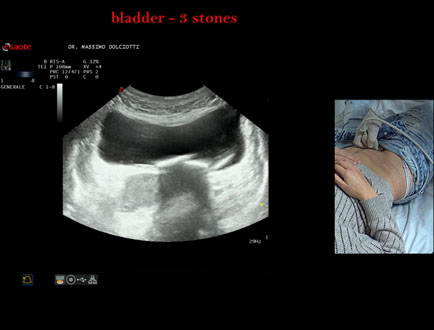

Data inserimento: 21/10/2025

Ecografia del: 15/10/2025

Strumento: Esaote MyLab Eight

Sonda: Convex Multifrequenza 1-8 MHz

Età Paziente: F 45 anni

Motivazione dell'esame: da alcuni mesi, disuria ed infezioni urinarie recidivanti.

Commento all'esame: le immagini ed il video documentano 3 immagini iperecogene, con cono d'ombra posteriore, da ricondurre a litiasi multipla della vescica.

Conclusioni: 3 calcoli della vescica (3 bladder stones).